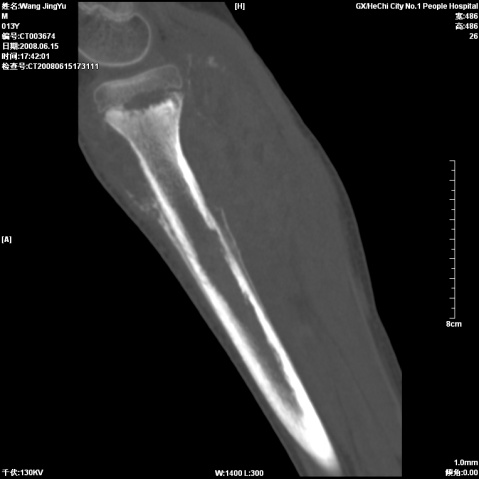

以下是引用随光逐影在2008-6-23 15:30:00的发言:[br]胫骨中上段骨肉瘤(临床表现:好发年龄+好发部位。ct表现:骨质破坏+肿瘤新生骨+骨膜反应并破坏,形成codman氏三角+软组织肿块)。